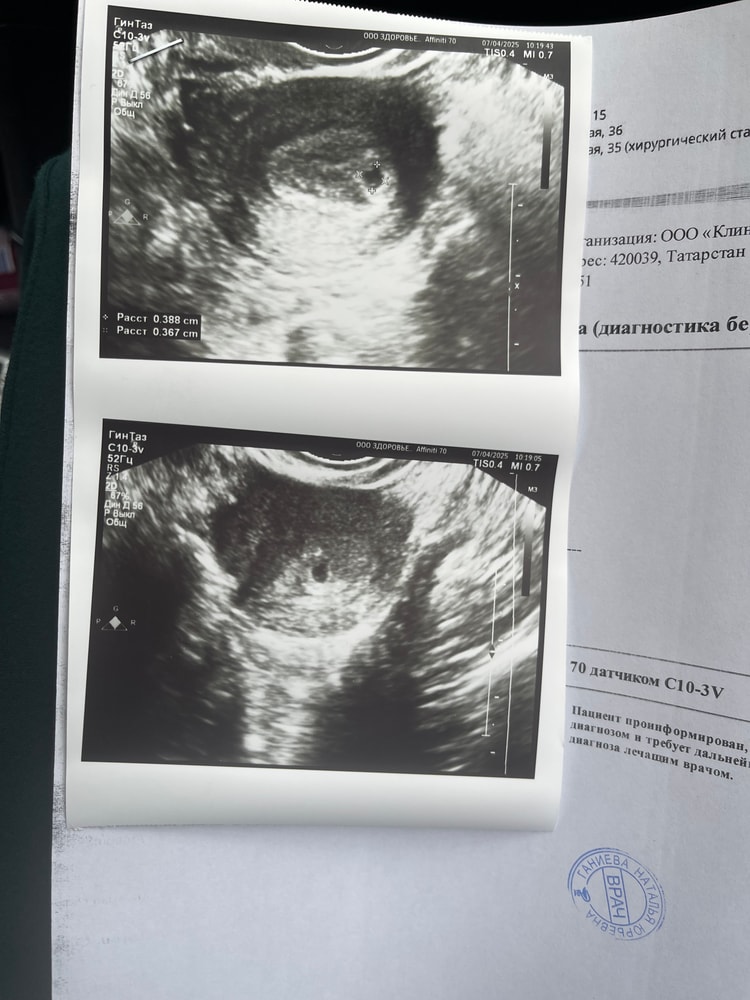

Беременность в матке

Тройня или киста? Беременность после вакуум аспирации